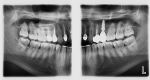

The practice has been able to follow this case for more than 6 years since its completion, and the tooth has remained comfortable and vital to thermal pulpal testing with no adverse responses to percussion or palpation. A 57-month posttreatment radiograph (extraoral view) demonstrates no radiographic evidence of pulpal pathosis (Figure 8).